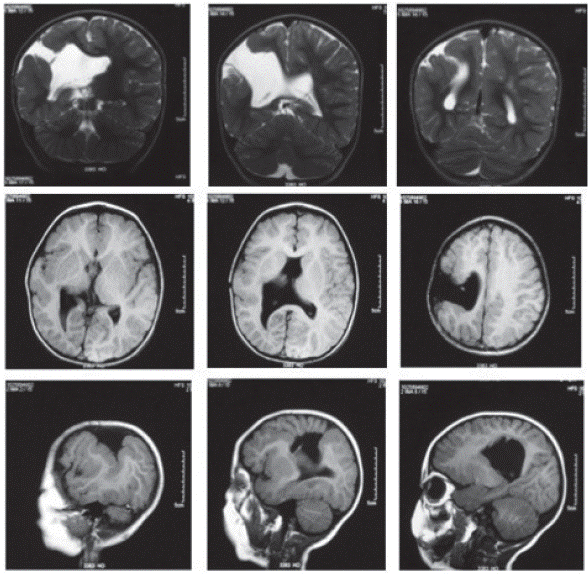

Al alta hospitalaria se determinó el diagnóstico de esquizencefalia de labio abierto fronto parietal derecho de origen desconocido (posible etiología genética asociada al gen EMX2 según concepto de genética) y hemiparesia izquierda. Continuó en seguimiento ambulatorio por Neurología pediátrica, quien solicitó al año y medio de vida RM (figura 1). Fue remitido desde esta edad a Neuro-rehabilitación para ajustar proceso de habilitación motora.

Figura 1 RM cerebral simple Esquizencefalia de labio abierto, parietal derecha. Hendidura recubierta por sustancia gris displásica, que comunica el espacio subaracnoideo de la convexidad frontoparietal derecha con el ventrículo lateral correspondiente. Ausencia de septo pelúcido.